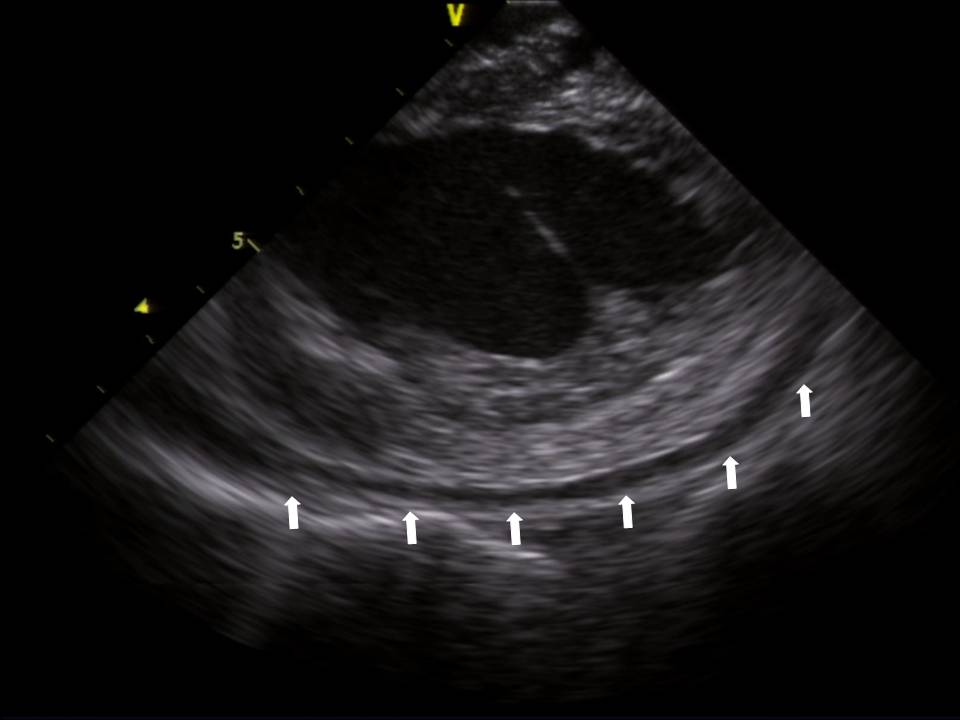

Use of ICE to Eliminate Radiation During AF Ablation

2015-07-24 13:06